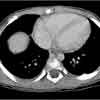

In view of these findings, a CT scan of the abdomen with contrast was done for suspected liver injury.

CT scans revealed a healing left posterior seventh rib fracture, which points to inflicted injury. A skeletal survey confirmed the finding of a single healing fracture of the posterior seventh rib. An ophthalmologic examination ruled out retinal hemorrhages.

CT scanning is a valuable adjunct. However, no studies that compare CT with established imaging modalities for the detecting of nonaccidental skeletal injury have been reported to date.1

An ataxic gait in our 2-year-old patient led to a laboratory workup that revealed markedly elevated liver enzyme levels. An investigation into the cause of ultimately led to the finding of a posterior rib fracture.